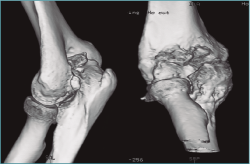

Las pruebas de imagen más útiles en este contexto son la radiografía simple (Figura 3) y la tomografía computarizada (TC) (Figuras 4 y 5), que evalúan la congruencia de las superficies articulares, la presencia de osteofitos u osificación ectópica, o alteraciones de la alineación ósea. Además, se evaluará la consolidación de fracturas previas, si es el caso, o la posible implicación del material de osteosíntesis en la falta de movilidad (si está correctamente situado, no tiene por qué interferir con la movilidad del codo)(6).

Figura 4. Artrosis de codo con formación osteofítica exuberante y fibrosis capsular, sin alteración del espacio o alineación articular, como ejemplo de rigidez extrínseca.